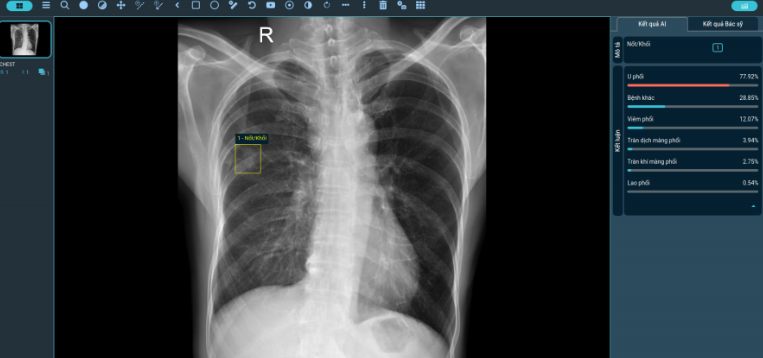

- Ứng dụng trí tuệ nhân tạo (AI) trong đọc phim X-quang phổi: hỗ trợ phát hiện sớm các tổn thương nghi lao;